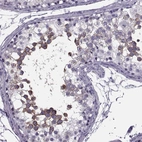

Immunohistochemistry analysis in human testis and kidney tissues using HPA030075 antibody. Corresponding SYNGR4 RNA-seq data are presented for the same tissues.